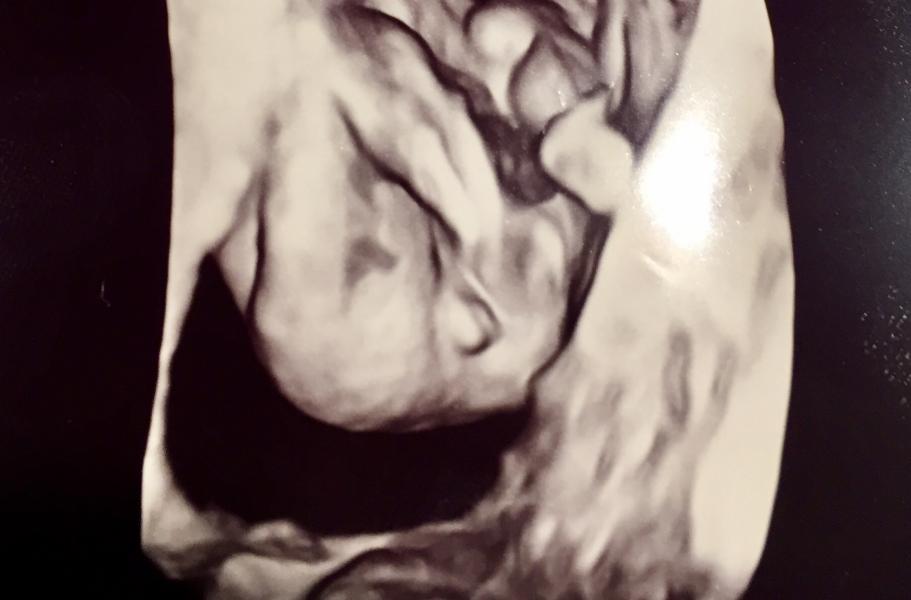

Дамы вот такое 3д мне сегодня выдали . Серьёзно озадачены с мужем какойже пол у нашего малыша ? Дело в том что опытная узист говорит что это половые губы девочки ??!!!! Мы в замешательстве

Тут надо обращать внимание не на то, насколько выпирают половые органы , а на полоску между половниками. Как мне объяснил узист , половые губы выпирают примерно одинаково на маленьких сроках с яичками. Но яички выглядят одним сплошным мешочком , без разделения на половинки. Так что если есть полоска посередине /- девочка. Наверное недель в 18-20 сходите ещё раз на УЗИ для точного результата.

Больше похоже что это яйки🙈 но слышала что до какого то срока у них там сложно отличить, вроде похоже слишком все.

Да вот не факт что мальчик! На этом сроке у них реально очень похожи половые органы. Мне кажется это девочка!

Ну форма у половых губ и яичек немного отличается)) я думаю мальчик

Похоже орешки - это она ножкой шевелила и пяточка размазалась ) а так чёрная полосочка по середине похожа на половые губы :) тем более узистка наверняка с разных сторон смотрела )